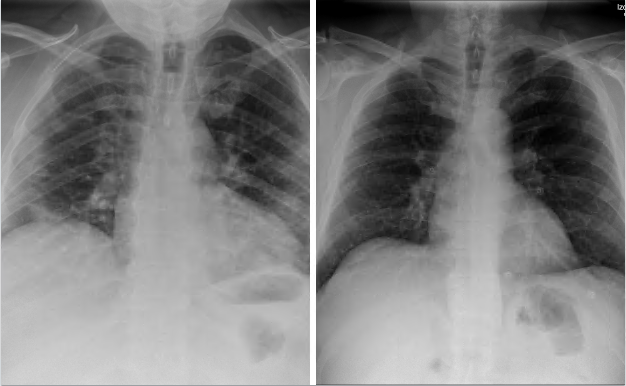

El algoritmo desarrollado por los investigadores de la Universidad de Granada (UGR) puede predecir el grado de afectación de los pulmones en pacientes diagnosticados de covid-19. Lo hace partiendo de la comparación de cientos de imágenes radiográficas pulmonares, tanto de pacientes con coronavirus asintomáticos como aquellos con una afectación grave. «Cuando hay una infección pulmonar, en la imagen aparece una nube blanca, que es de mayor tamaño (de abajo hacia arriba) según lo infectado que esté el órgano», explica Francisco Herrera. Se distinguen cuatro situaciones de gravedad según cómo está de propagada la infección. Cada pulmón se divide en cuatro regiones (lo que suman un total de ocho entre ambos). Una infección severa es la que afecta, almenos, a seis de estas regiones, mientras que una leve implica dos regiones afectadas. El algoritmo tiene una precisión de más del 80% y, más adelante, este mismo modelo pretende utilizarse para distinguir todo tipo de enfermedades pulmonares víricas o bacterianas, como la neumonía.

Comparación de dos radiografías pulmonares. Izquierda: pulmones infectados de coronavirus. Derecha: pulmones sanos. Imagen cedida por Francisco Herrera